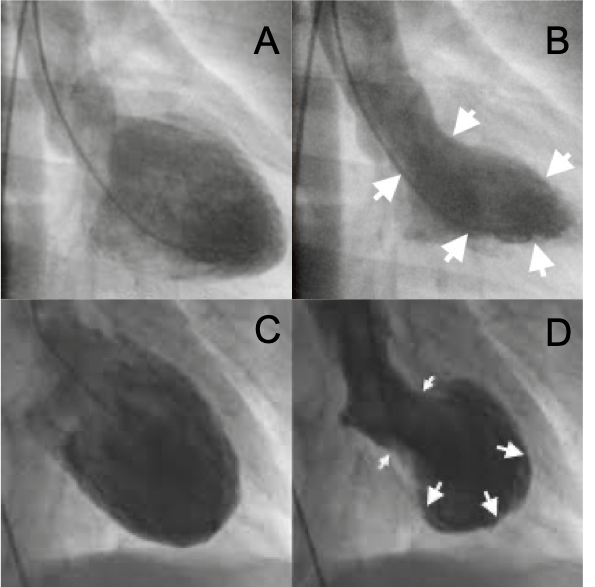

- En las pruebas de imagen (ecocardiograma o resonancia magnética) se puede identificar un movimiento anormal de la pared del ventrículo izquierdo conocido como «apical ballooning» o abombamiento apical, que es muy característico de la cardiomiopatía de estrés.

Curiosamente, de la similitud entre la imagen ventriculográfica de un abombamiento apical y un takotsubo* le viene el nombre a este síndrome.